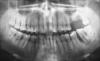

Дядя Вик Опубликовано 16 ноября, 2006 Поделиться Опубликовано 16 ноября, 2006 Uncle Vik, a zachem zhdat' ,kogda tam i tak uzhe bifurkatsii i kostnye karmany? Ubrat' vsyu "beznadegu", delat' surgery s kostnoi podsadkoi.Karies kornya dist. v 12? Качество снимка не позволяет судить об кариесе корня 12, сами понимаете. Что касается ожидания, то я стараюсь пролечить в начале без surgery, если динамика плохая, то тогда конечно оно нужно. Любая операция стоит дорого и т.д. Я всегда пробую 4 мес повести пациента таким вот образом. Про периочип читал в соседнем форуме , у нас продается ли? кто применяет.есть отзывы? Продается или нет в РФ не знаю, но я им работаю и отзывы просто СУПЕР, идет уже на 1-2 месяце положительная динамика, RG ++, мне очень он пока нравится, хотя и дорогой. От хлоргексидина вреда пока что еще не было. Ссылка на комментарий

lev Опубликовано 17 ноября, 2006 Поделиться Опубликовано 17 ноября, 2006 Качество снимка не позволяет судить об кариесе корня 12, сами понимаете. Что касается ожидания, то я стараюсь пролечить в начале без surgery, если динамика плохая, то тогда конечно оно нужно. Любая операция стоит дорого и т.д. Я всегда пробую 4 мес повести пациента таким вот образом. Продается или нет в РФ не знаю, но я им работаю и отзывы просто СУПЕР, идет уже на 1-2 месяце положительная динамика, RG ++, мне очень он пока нравится, хотя и дорогой. От хлоргексидина вреда пока что еще не было. Opyat' ya pereputal klassifikatsii: ne 12 , a 17 s kariesom, po- moemu ochen' horosho vidno. Ссылка на комментарий